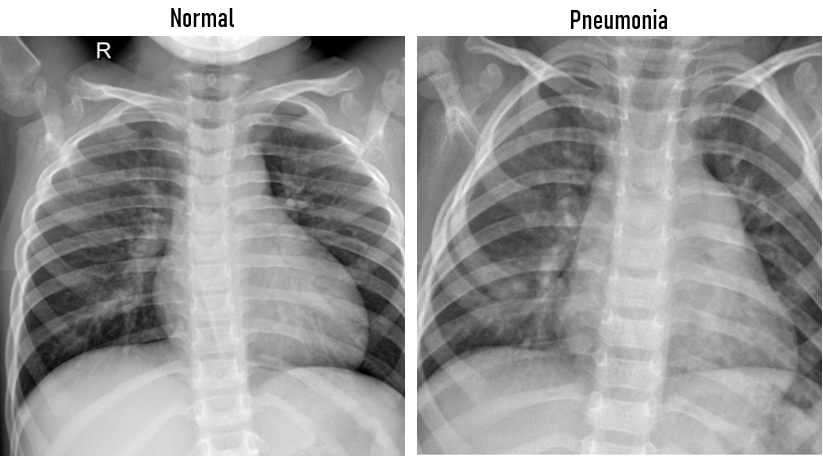

The dataset consists of 3 subdirectories, namely train, val and test with each of them containing chest X-Ray images of two classes of interest i.e. Normal and Pneumonia.

The train set has about 4877 images, with 3707 images of Pneumonia and 1176 images of Normal Chest X-Ray Image. The val set has around 349 image files, with Normal constituting about 173 files and Pneumonia composed of 176 images. The test set consists of 624 images, with 234 Normal images and 390 Pneumonia images.